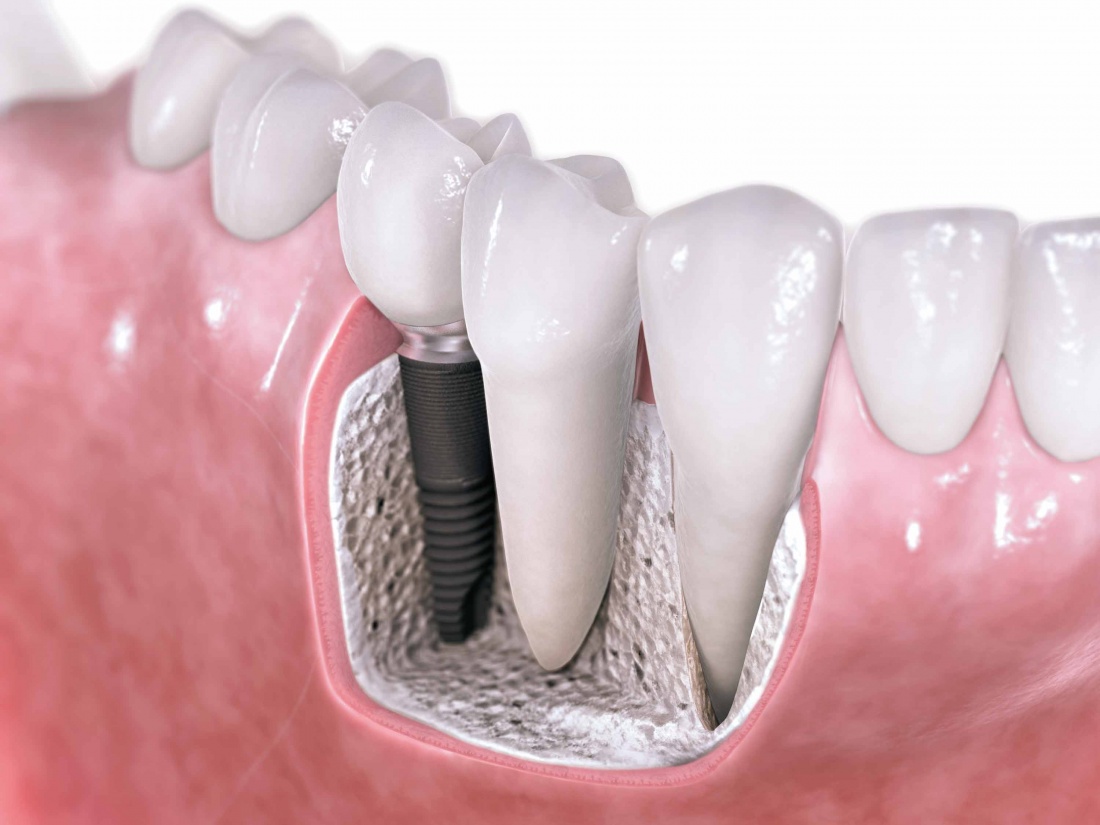

Цель имплантологического лечения — не воткнуть импланты так, чтобы они прижились, а создание надёжной и долговечной опоры под планируемую ортопедическую конструкцию.